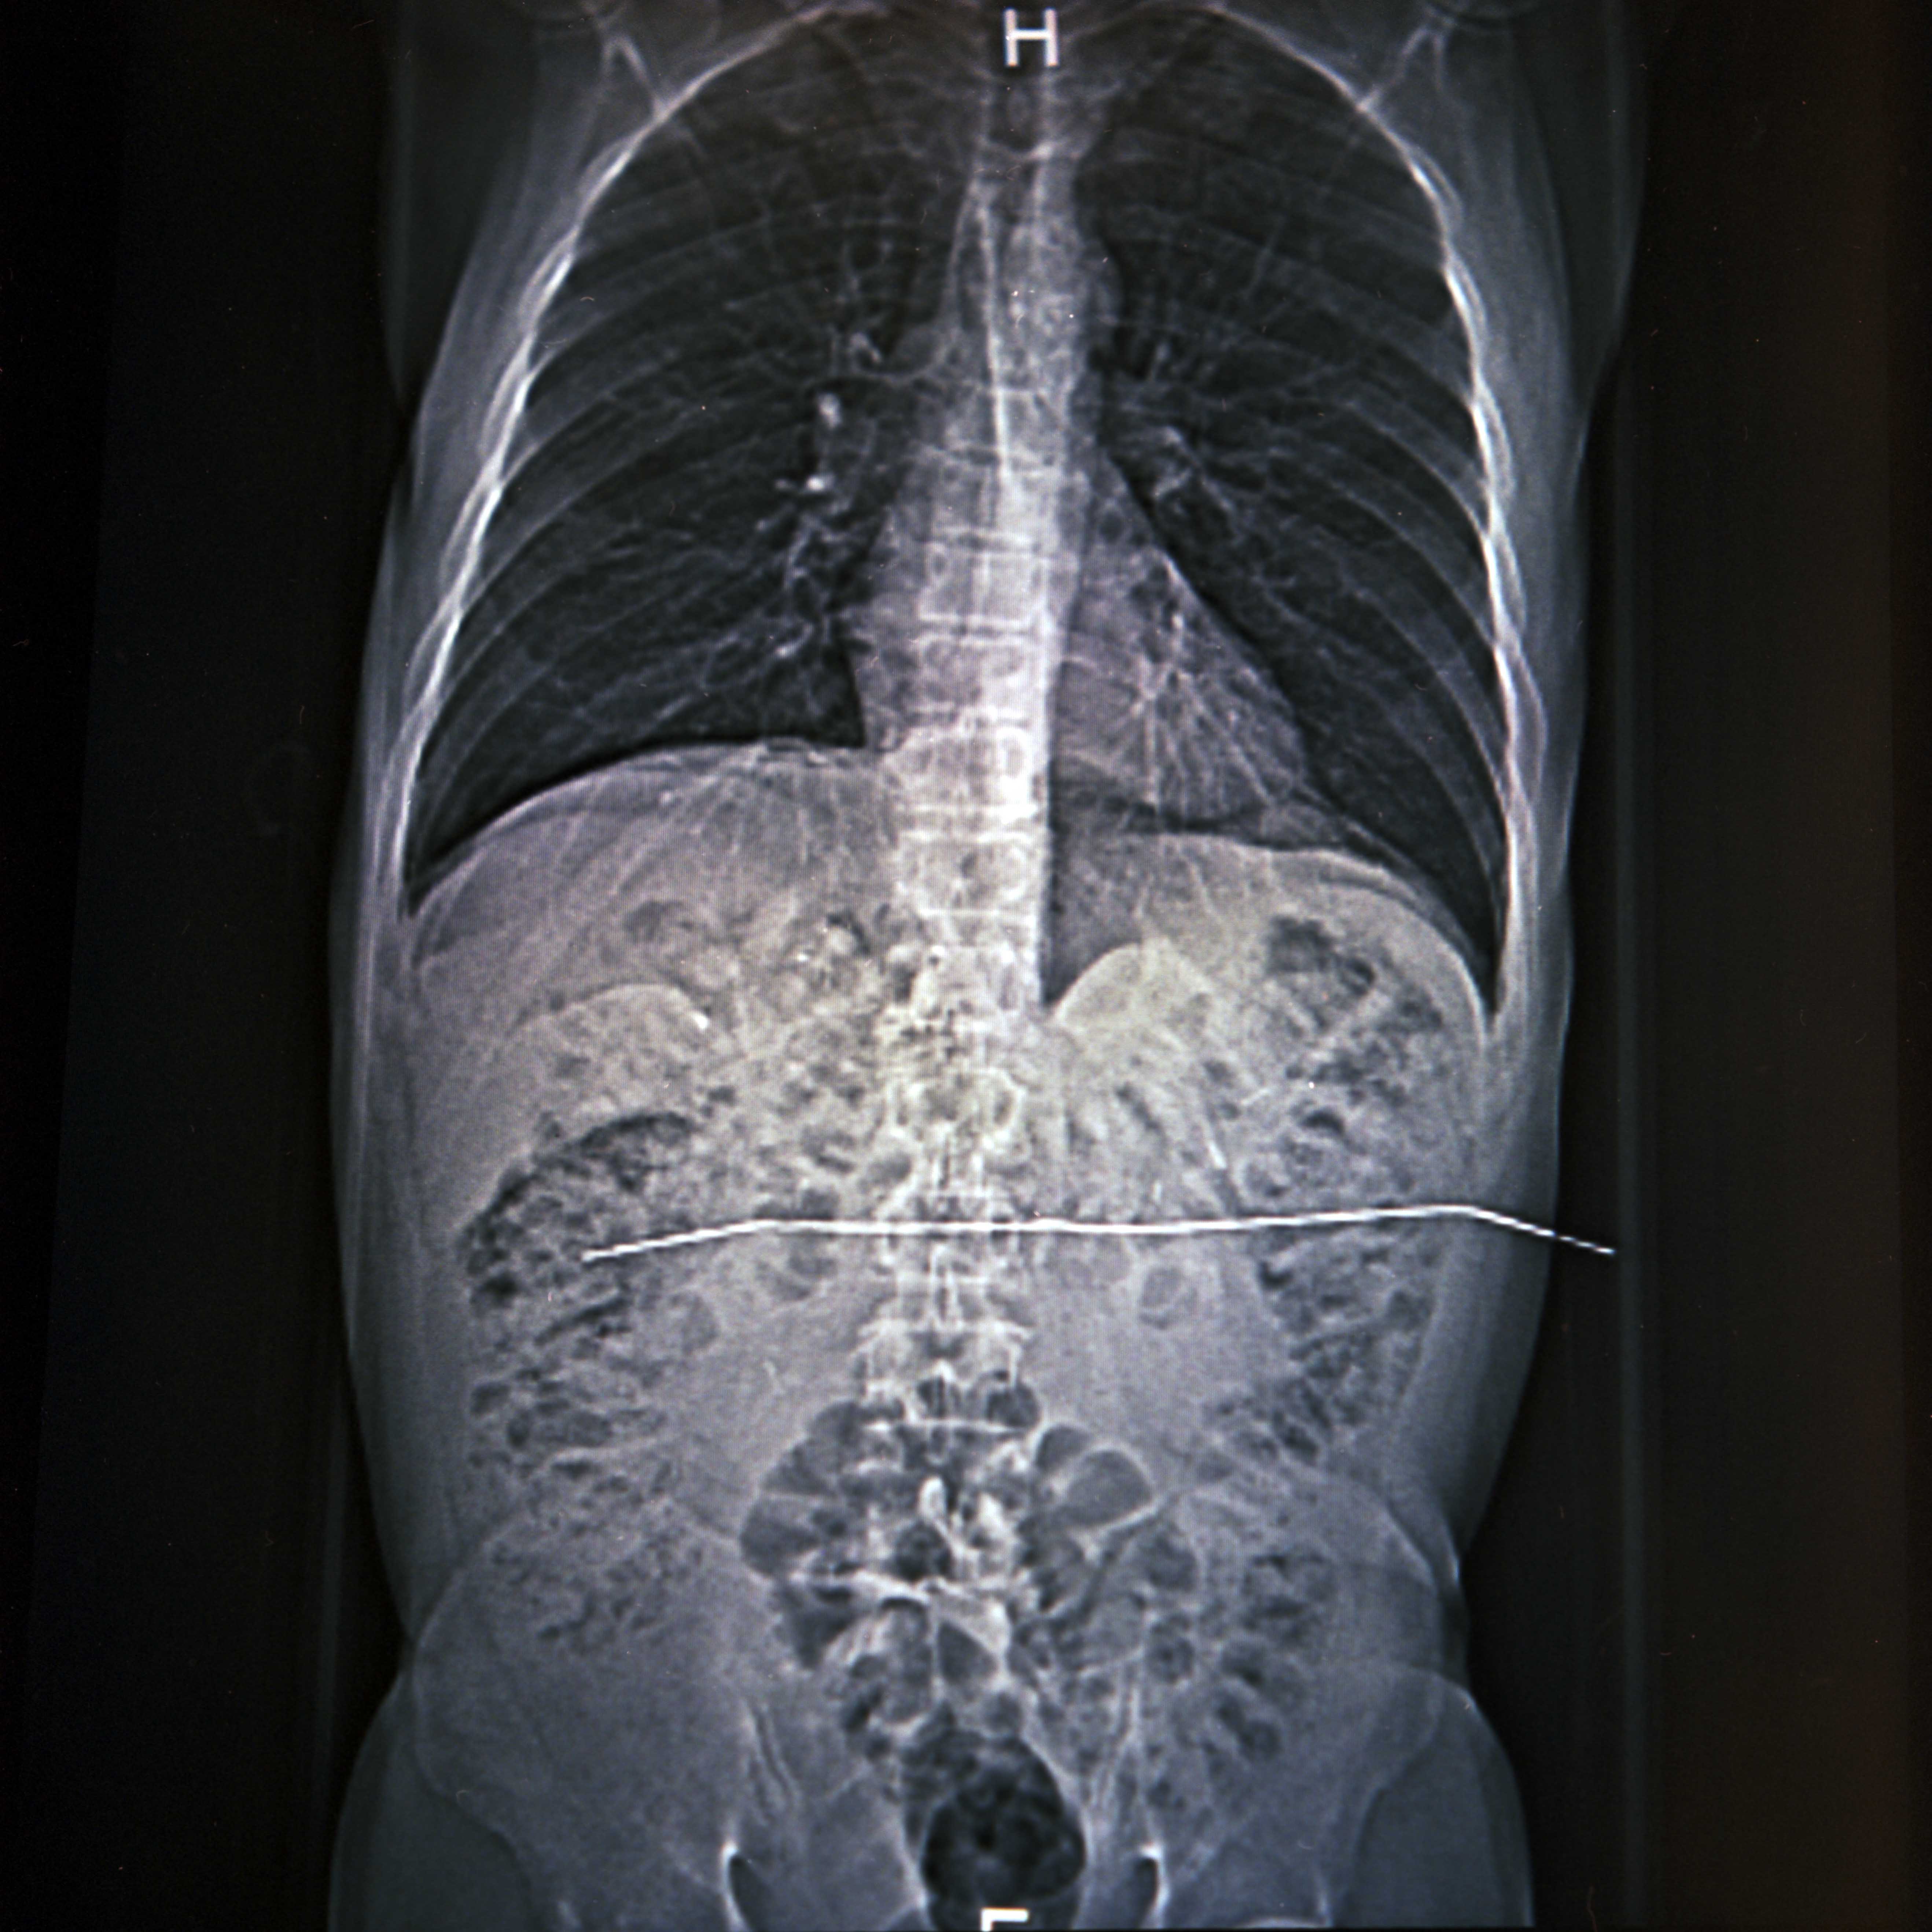

Papá